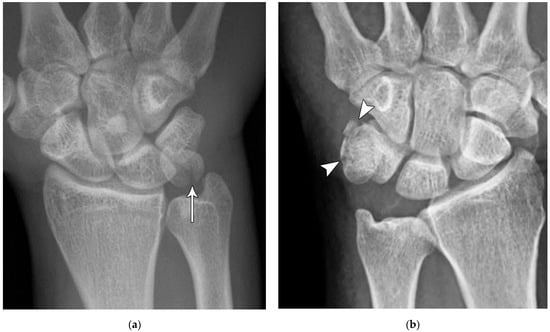

Figure 4. (a) Lateral radiograph of the wrist showing Humpback deformity (arrow) after a scaphoid fracture. (b) Sagittal CT reformation of the wrist showing the full extent of a humpback deformity with dorsal prominence at the site of the scaphoid fracture (arrowheads); image courtesy of Frank Gaillard, Radiopaedia.org, rID: 18269.

The majority of scaphoid fractures (70%) occur through the waist of the scaphoid, with 10% of scaphoid fractures involving the distal third, and 20% involving the proximal third (Figure 2 and Figure 3) [2,14]. With a scaphoid waist fracture, dorsal prominence at the fracture site due to dorsal angulation is known as humpback deformity (Figure 4). This deformity is important to recognize, as it needs to be more aggressively managed due to high risk of nonunion [15]. Additionally, if the two fragments unite with a humpback deformity, it may further destabilize the wrist. This humpback deformity may also be associated with dorsal intercalated segment instability (DISI), which will be covered in more detail later.